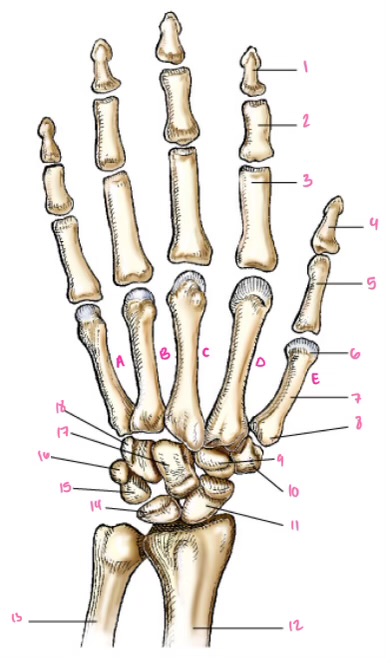

1

1

2

2

3

3

4

9

5

10

6

11

7

14

8

15

9

16

10

17

11

18

12

1

13

2

14

3

15

4

16

5

17

6

18

7

19

8

20

9

7

22

8

23

9

24

10

25

11

26

13

14

15

16

17